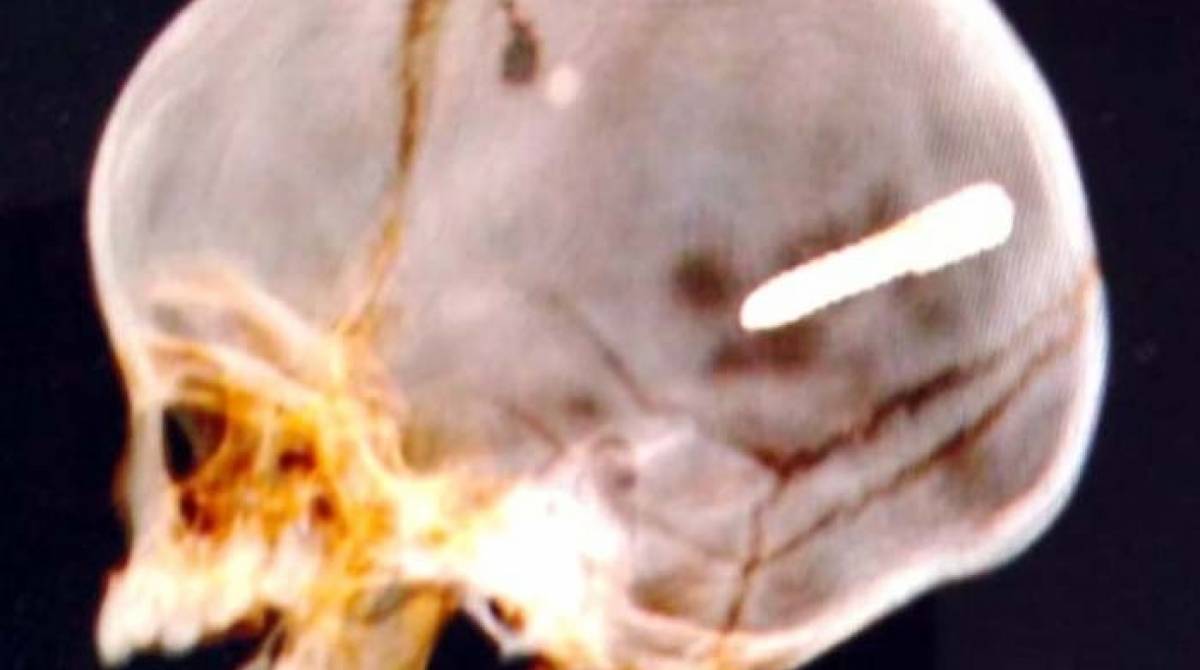

Exame de imagem constatou objeto alojado na cabeça do bebêREPRODUÇÕES/WhatsApp

Após o incidente, o menino seguiu para a UPA de Paciência e depois foi transferido para o Hospital Pedro II, em Santa Cruz. Uma tomografia computadorizada revelou que o objeto ficou alojado na cabeça dele. De acordo com a Secretaria Municipal de Saúde, o bebê passou por uma cirurgia nesta madrugada. No entanto, não resistiu aos ferimentos e faleceu nesta tarde.

"Devido à área do cérebro atendida, os neurocirurgiões consideraram não ser possível neste momento a retirada do projétil", a secretaria informou, em nota, nesta manhã.